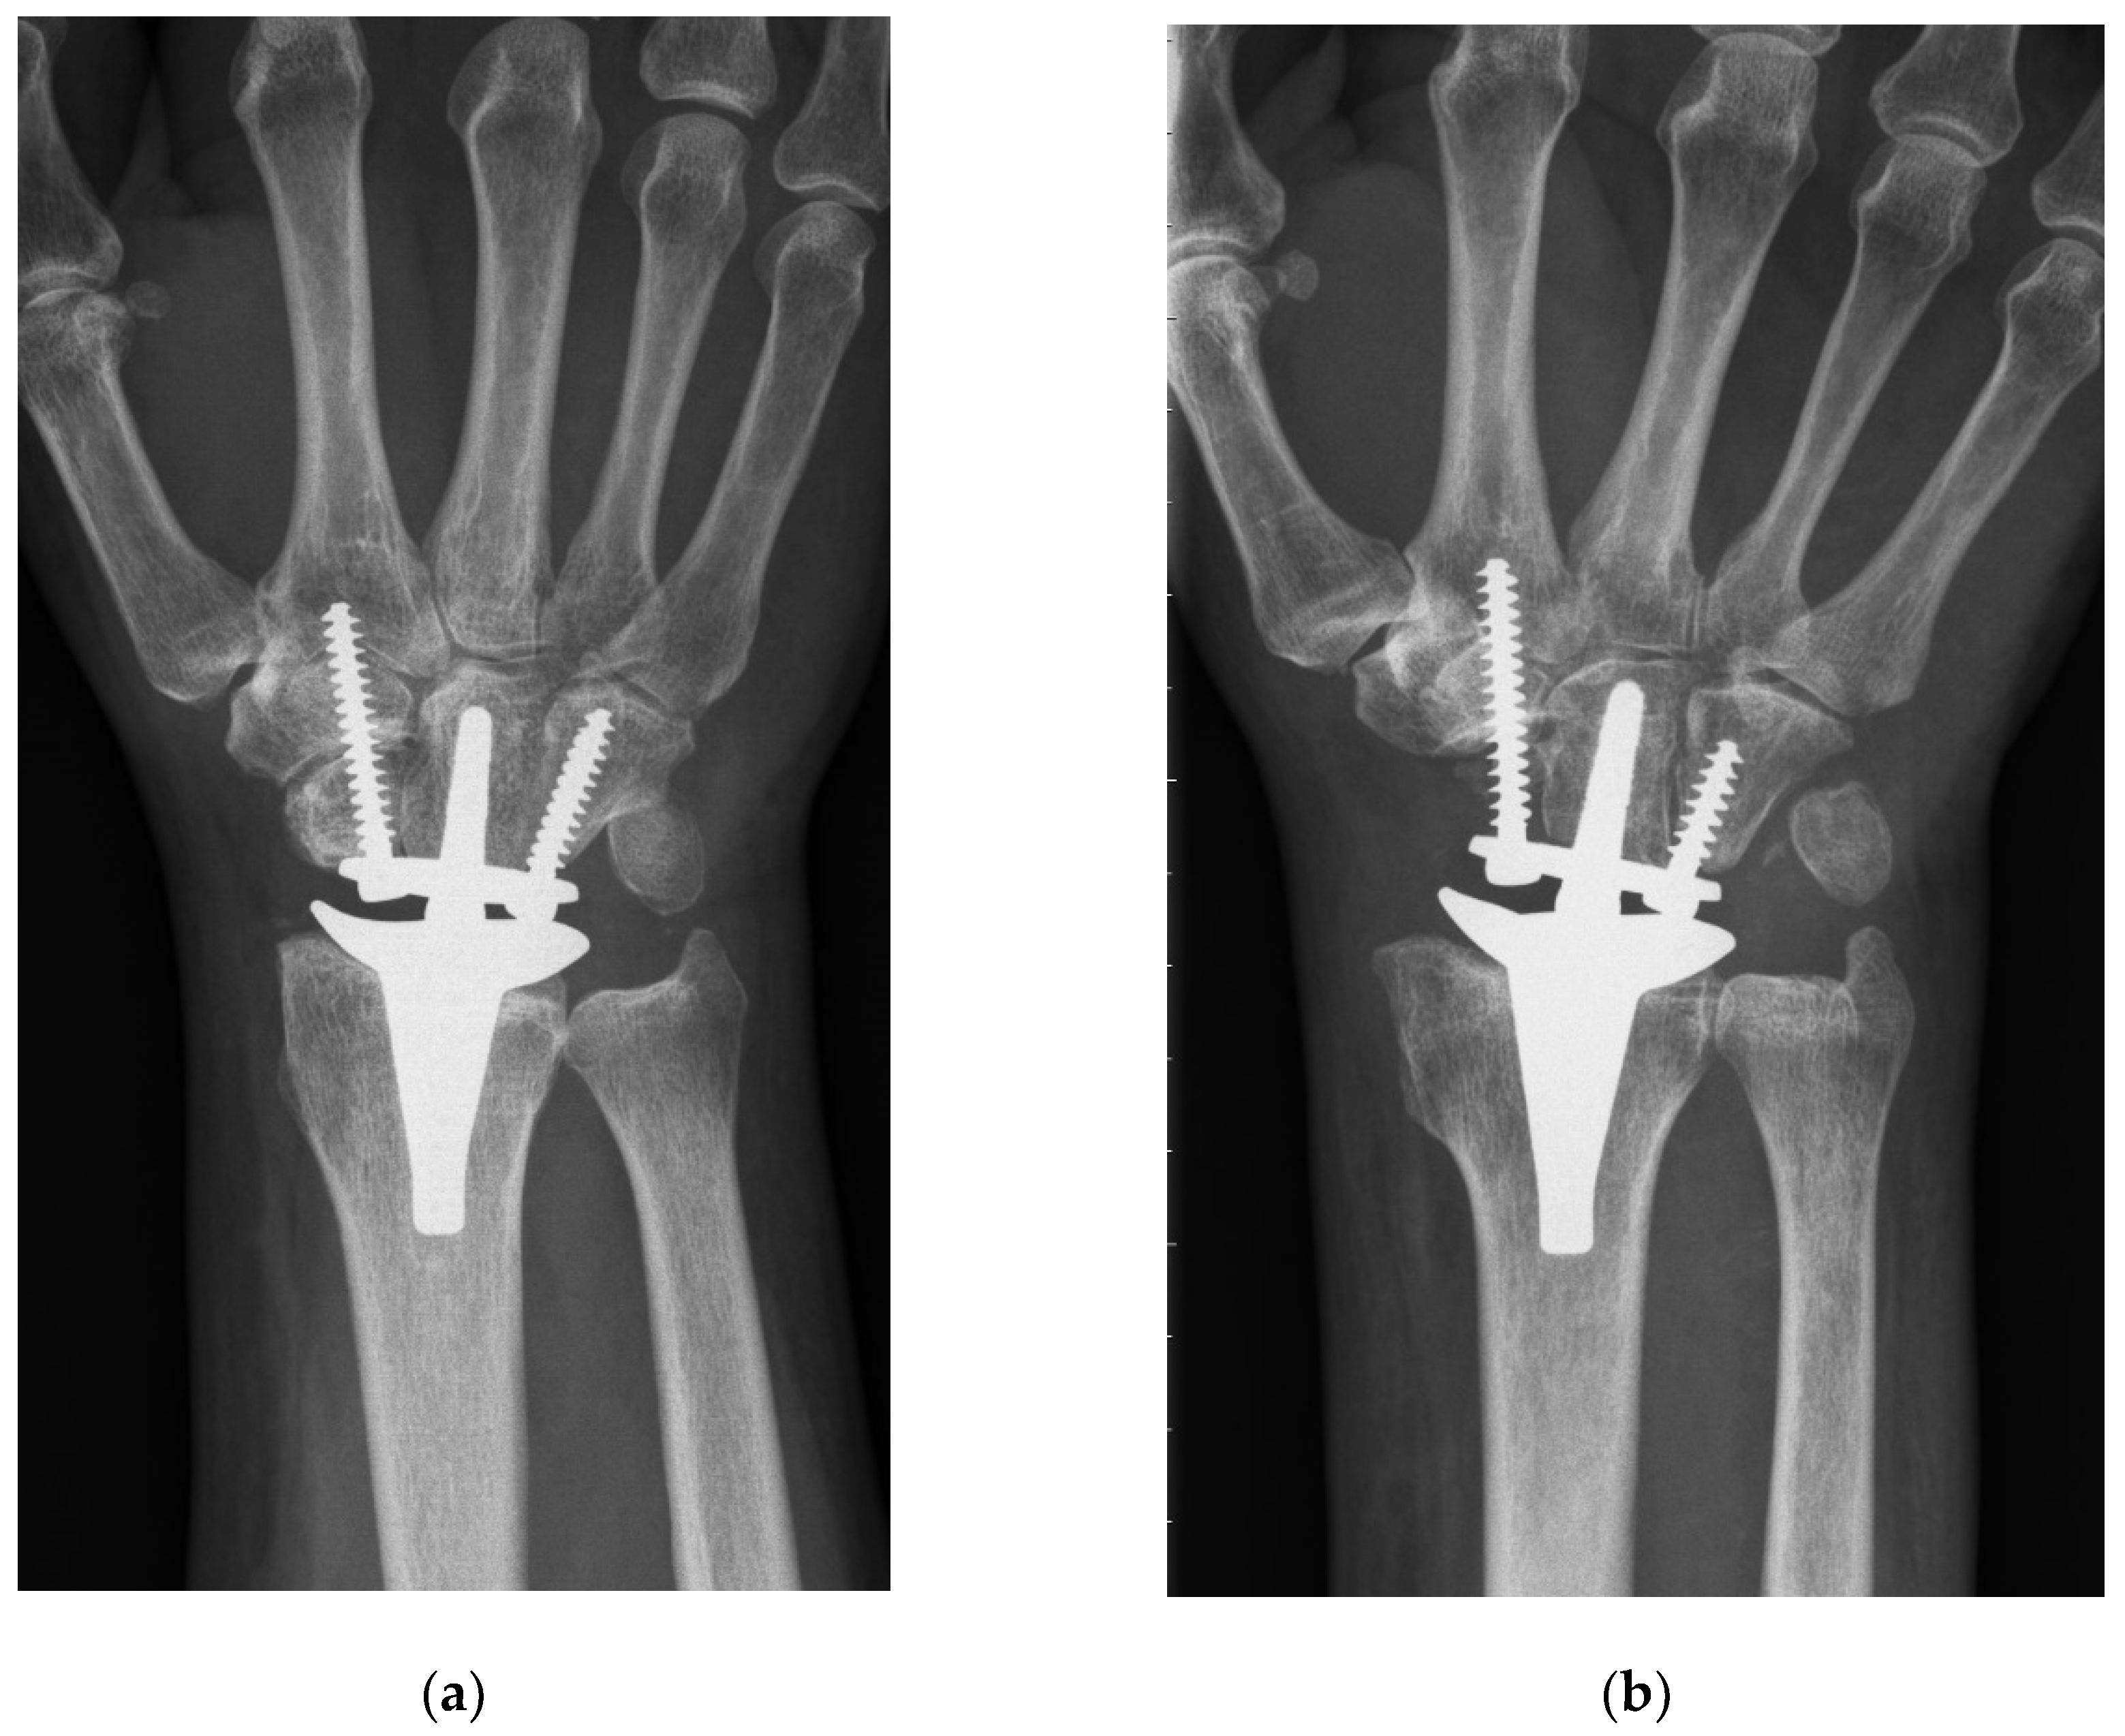

From www.mdpi.com

JCM Free FullText Proximal Row Carpectomy with Total Scapoidectomy Wrist Replacement Vs Fusion a wrist fusion surgery permanently fuses the bones in the wrist. doctors and researchers at the university of iowa compared treatment for patients with severe wrist arthritis. outcomes are compared with wrist fusion or arthrodesis, the alternative to wrist replacement. sometimes called arthroplasty, total wrist replacement involves removing damaged bones and cartilage in. Arthrodesis can get. Wrist Replacement Vs Fusion.